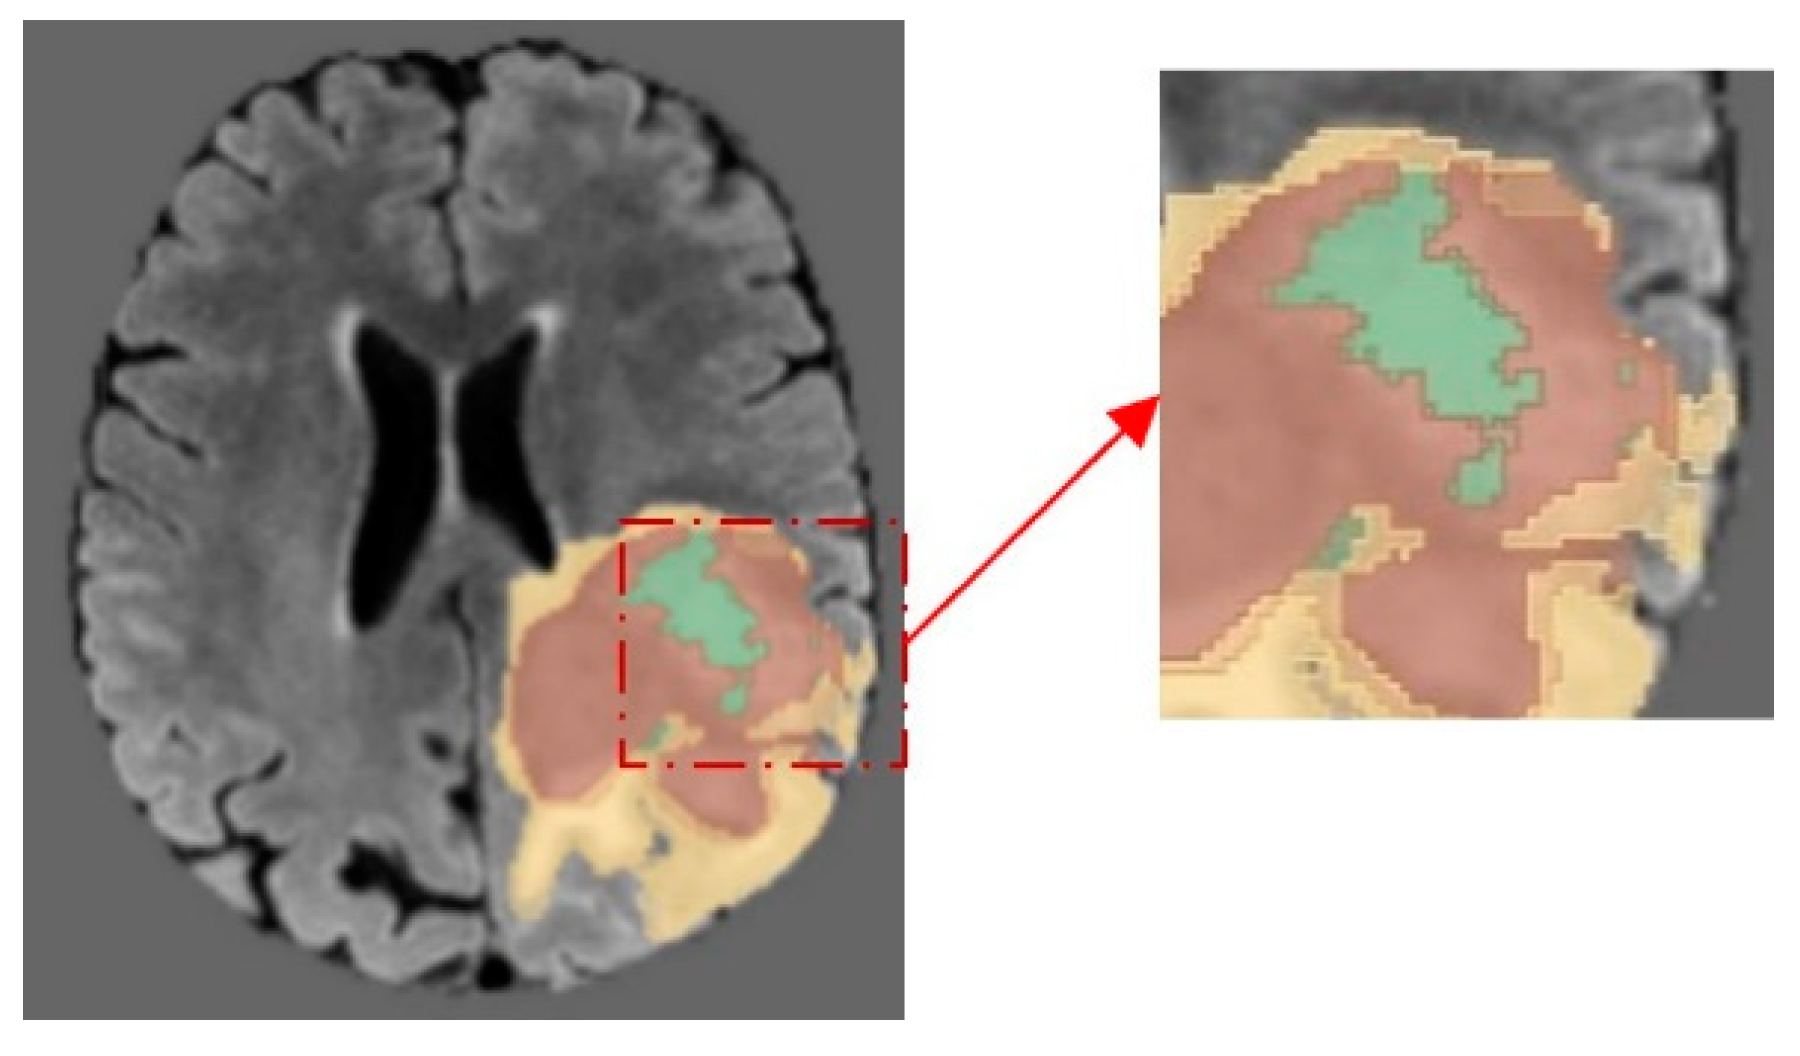

Previous medical image segmentation studies have encountered challenges in discerning different adjacent pathological areas. For instance, within the dataset employed in our investigation, distinguishing between the enhanced tumor (ET) and the edema/necrotic tissue (ED), as well as differentiating the necrotic tumor core (NCR) from the surrounding tissue, has been notably difficult.

Furthermore, the precise definition of the tumor lesion’s periphery continues to present a significant challenge in the field of medical image analysis in Figure 2. An enhanced attention mechanism is introduced which emphasizes the features of the edge regions. The attention module is operationalized through the following equation,

Figure 2. The differentiating the enhanced tumor (ET) from edema/necrotic tissue (ED) and delineating the necrotic tumor core (NCR) within the complexities of medical image segmentation.